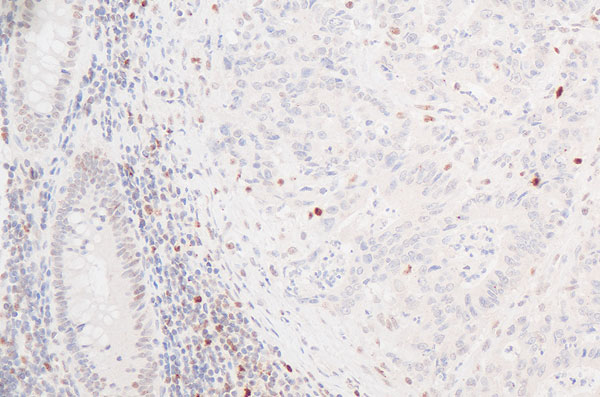

Prädiktive Tumordiagnostik:

Verlust des DNA-mismatch Reparaturproteins PMS2 in einem Kolonkarzinom (Mikrosatelliteninstabilität)